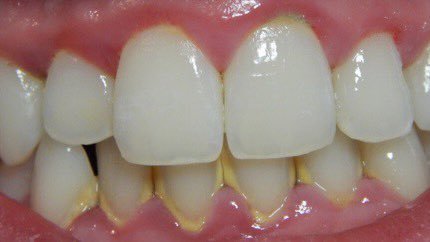

التهاب اللثة الخارجي(مرحلة١):

-الإنتفاخ

-الإحمرار

-النزف

-الألم

-سهل العلاج ويختفي تماماً